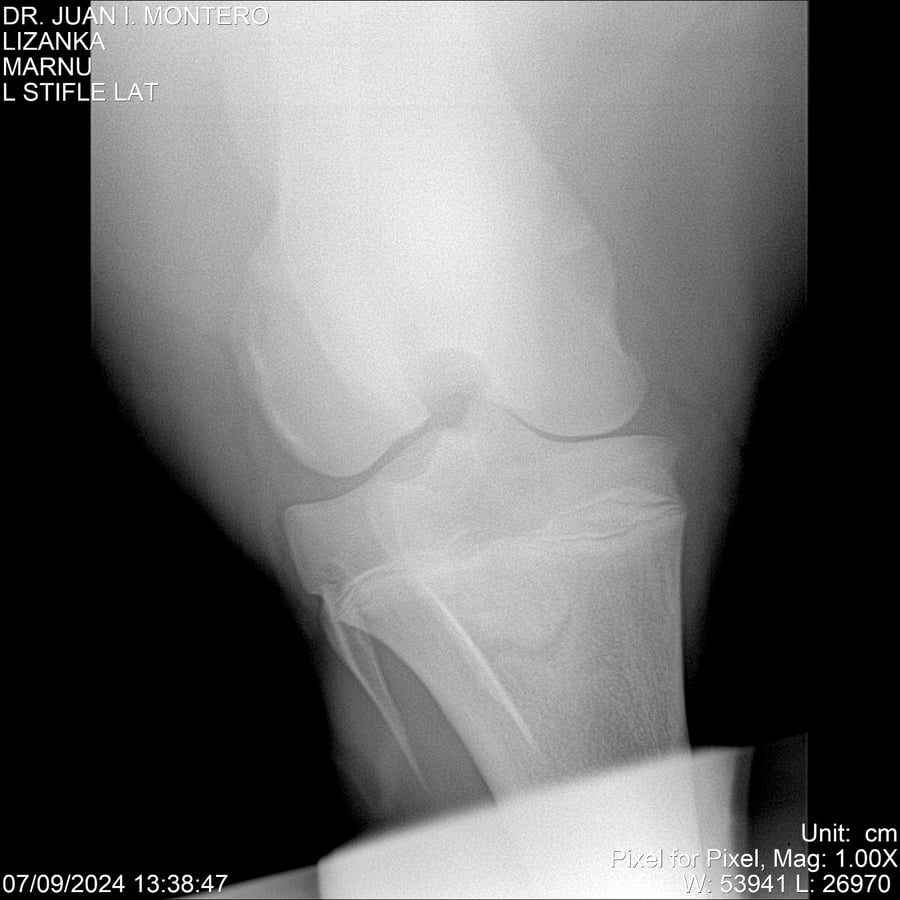

LOTE 18, LIZANKA Lote Anterior Volver al remate Lote Siguiente Ficha Contacto Montevideo - Ficha del Lote Identificador: #282512 Categoría: Yeguarizos Montevideo - 62 Visualizaciones ClicData Contacto Empresa: Abelenda N. R., Walter Hugo Nombre*: Teléfono* : E-mail* : Mensaje Enviar Registrese gratis Este contenido Exclusivo está disponible sólo para usuarios registrados Ingresar